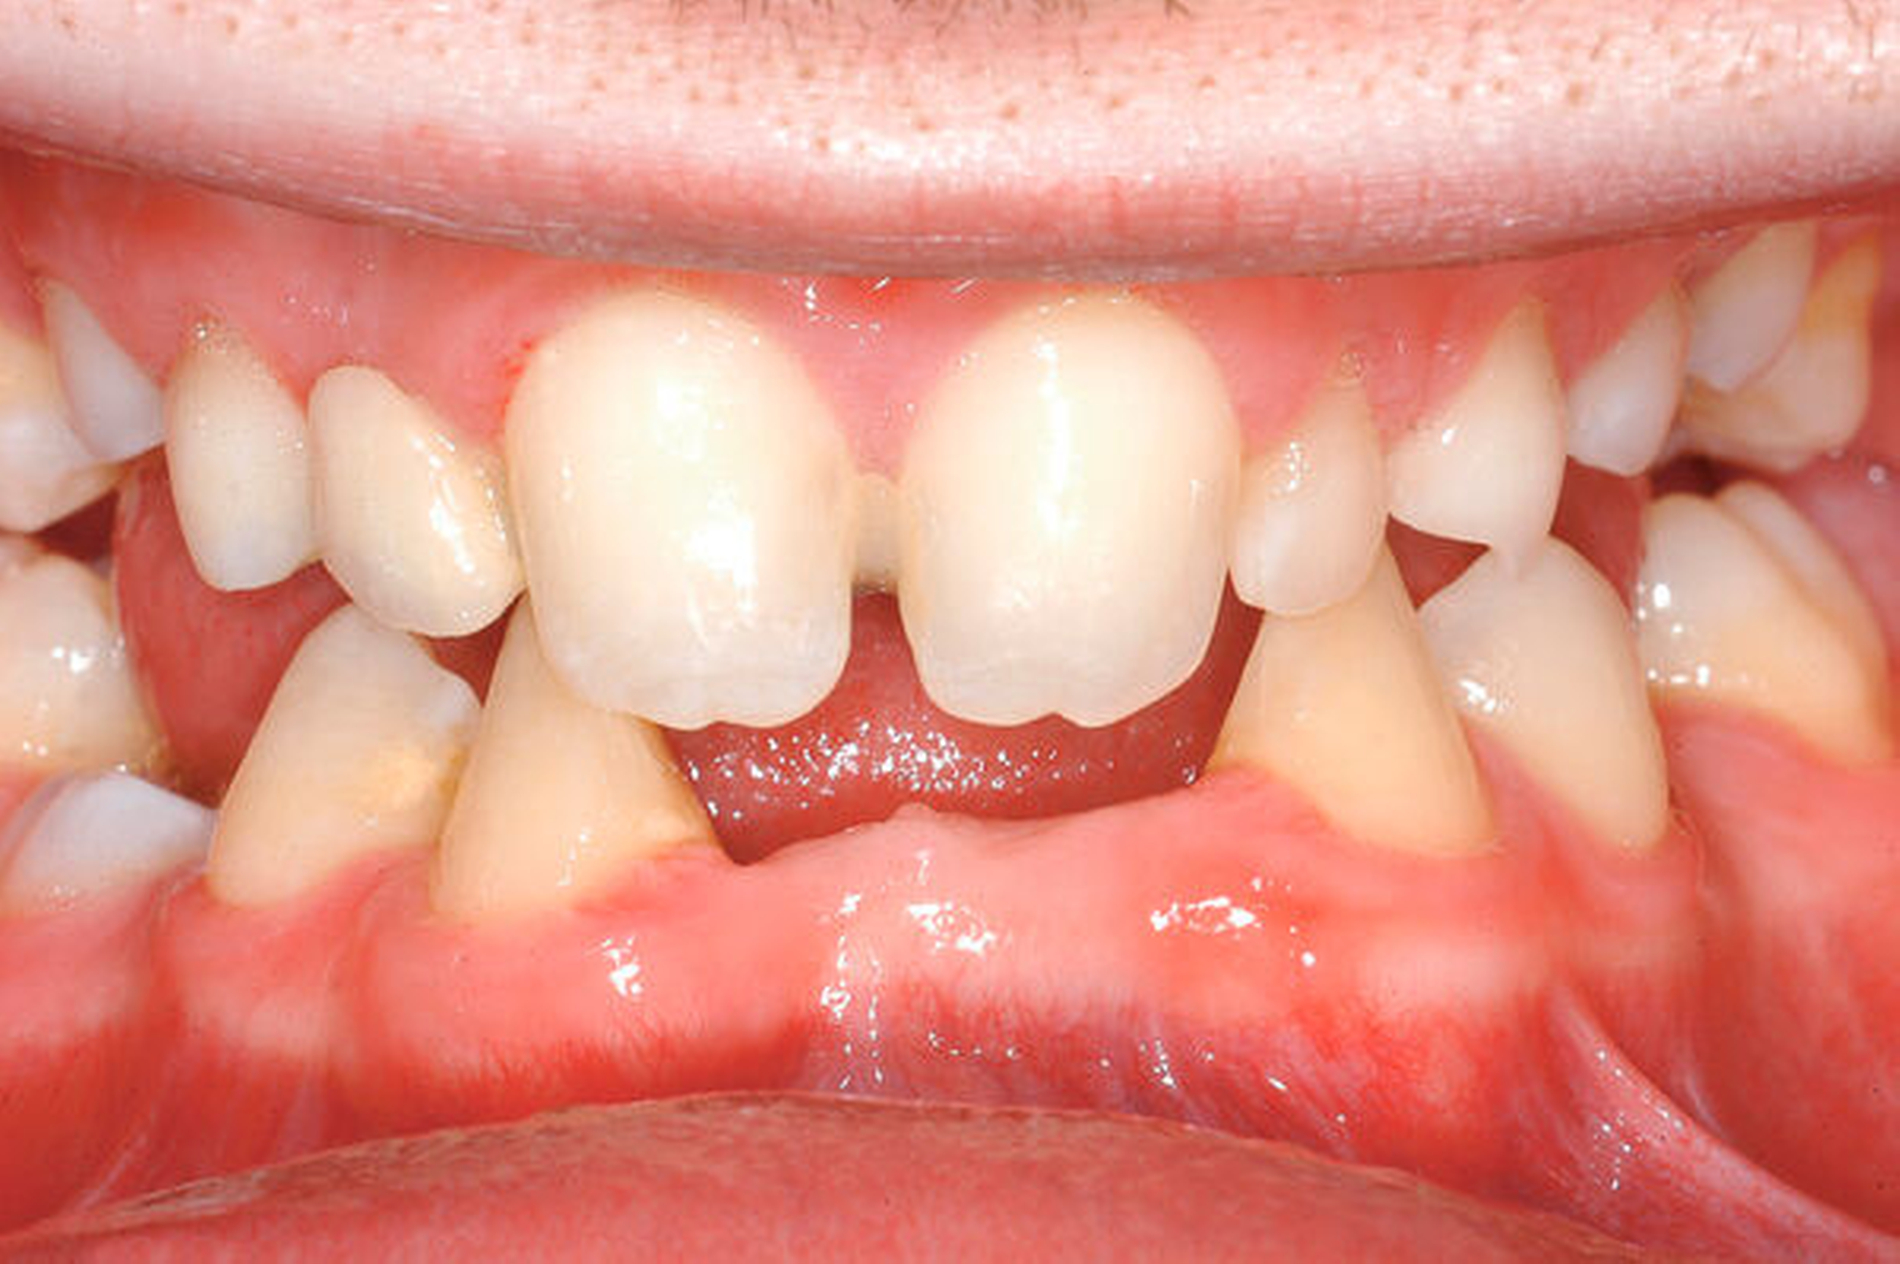

Beim intraoralen Befund imponierten neben multiplen Lücken ein partiell seitlich-offener Biss, eine auffällig konische Form der oberen mittleren Schneidezähne sowie persistierende Milchzähne (Abbildungen 2 bis 4). Zusammen mit der angefertigten Panoramaschichtaufnahme (Abbildung 5) konnte der Verdacht einer ausgeprägten Oligodontie bestätigt werden – insgesamt waren 22 Zähne inklusive der Weisheitszähne nicht angelegt. Auf Grundlage der bestehenden Befunde wurde der Verdacht einer genetischen Ursache der Symptome geäußert und dem Patienten zunächst eine molekulargenetische Abklärung mit der Verdachtsdiagnose „genetisch bedingte Zahnnichtanlagen / ektodermale Dysplasie“ empfohlen. Bei der Sequenzanalyse wurde eine Mutation im WNT10A-Gen nachgewiesen und somit die klinische Verdachtsdiagnose bestätigt.